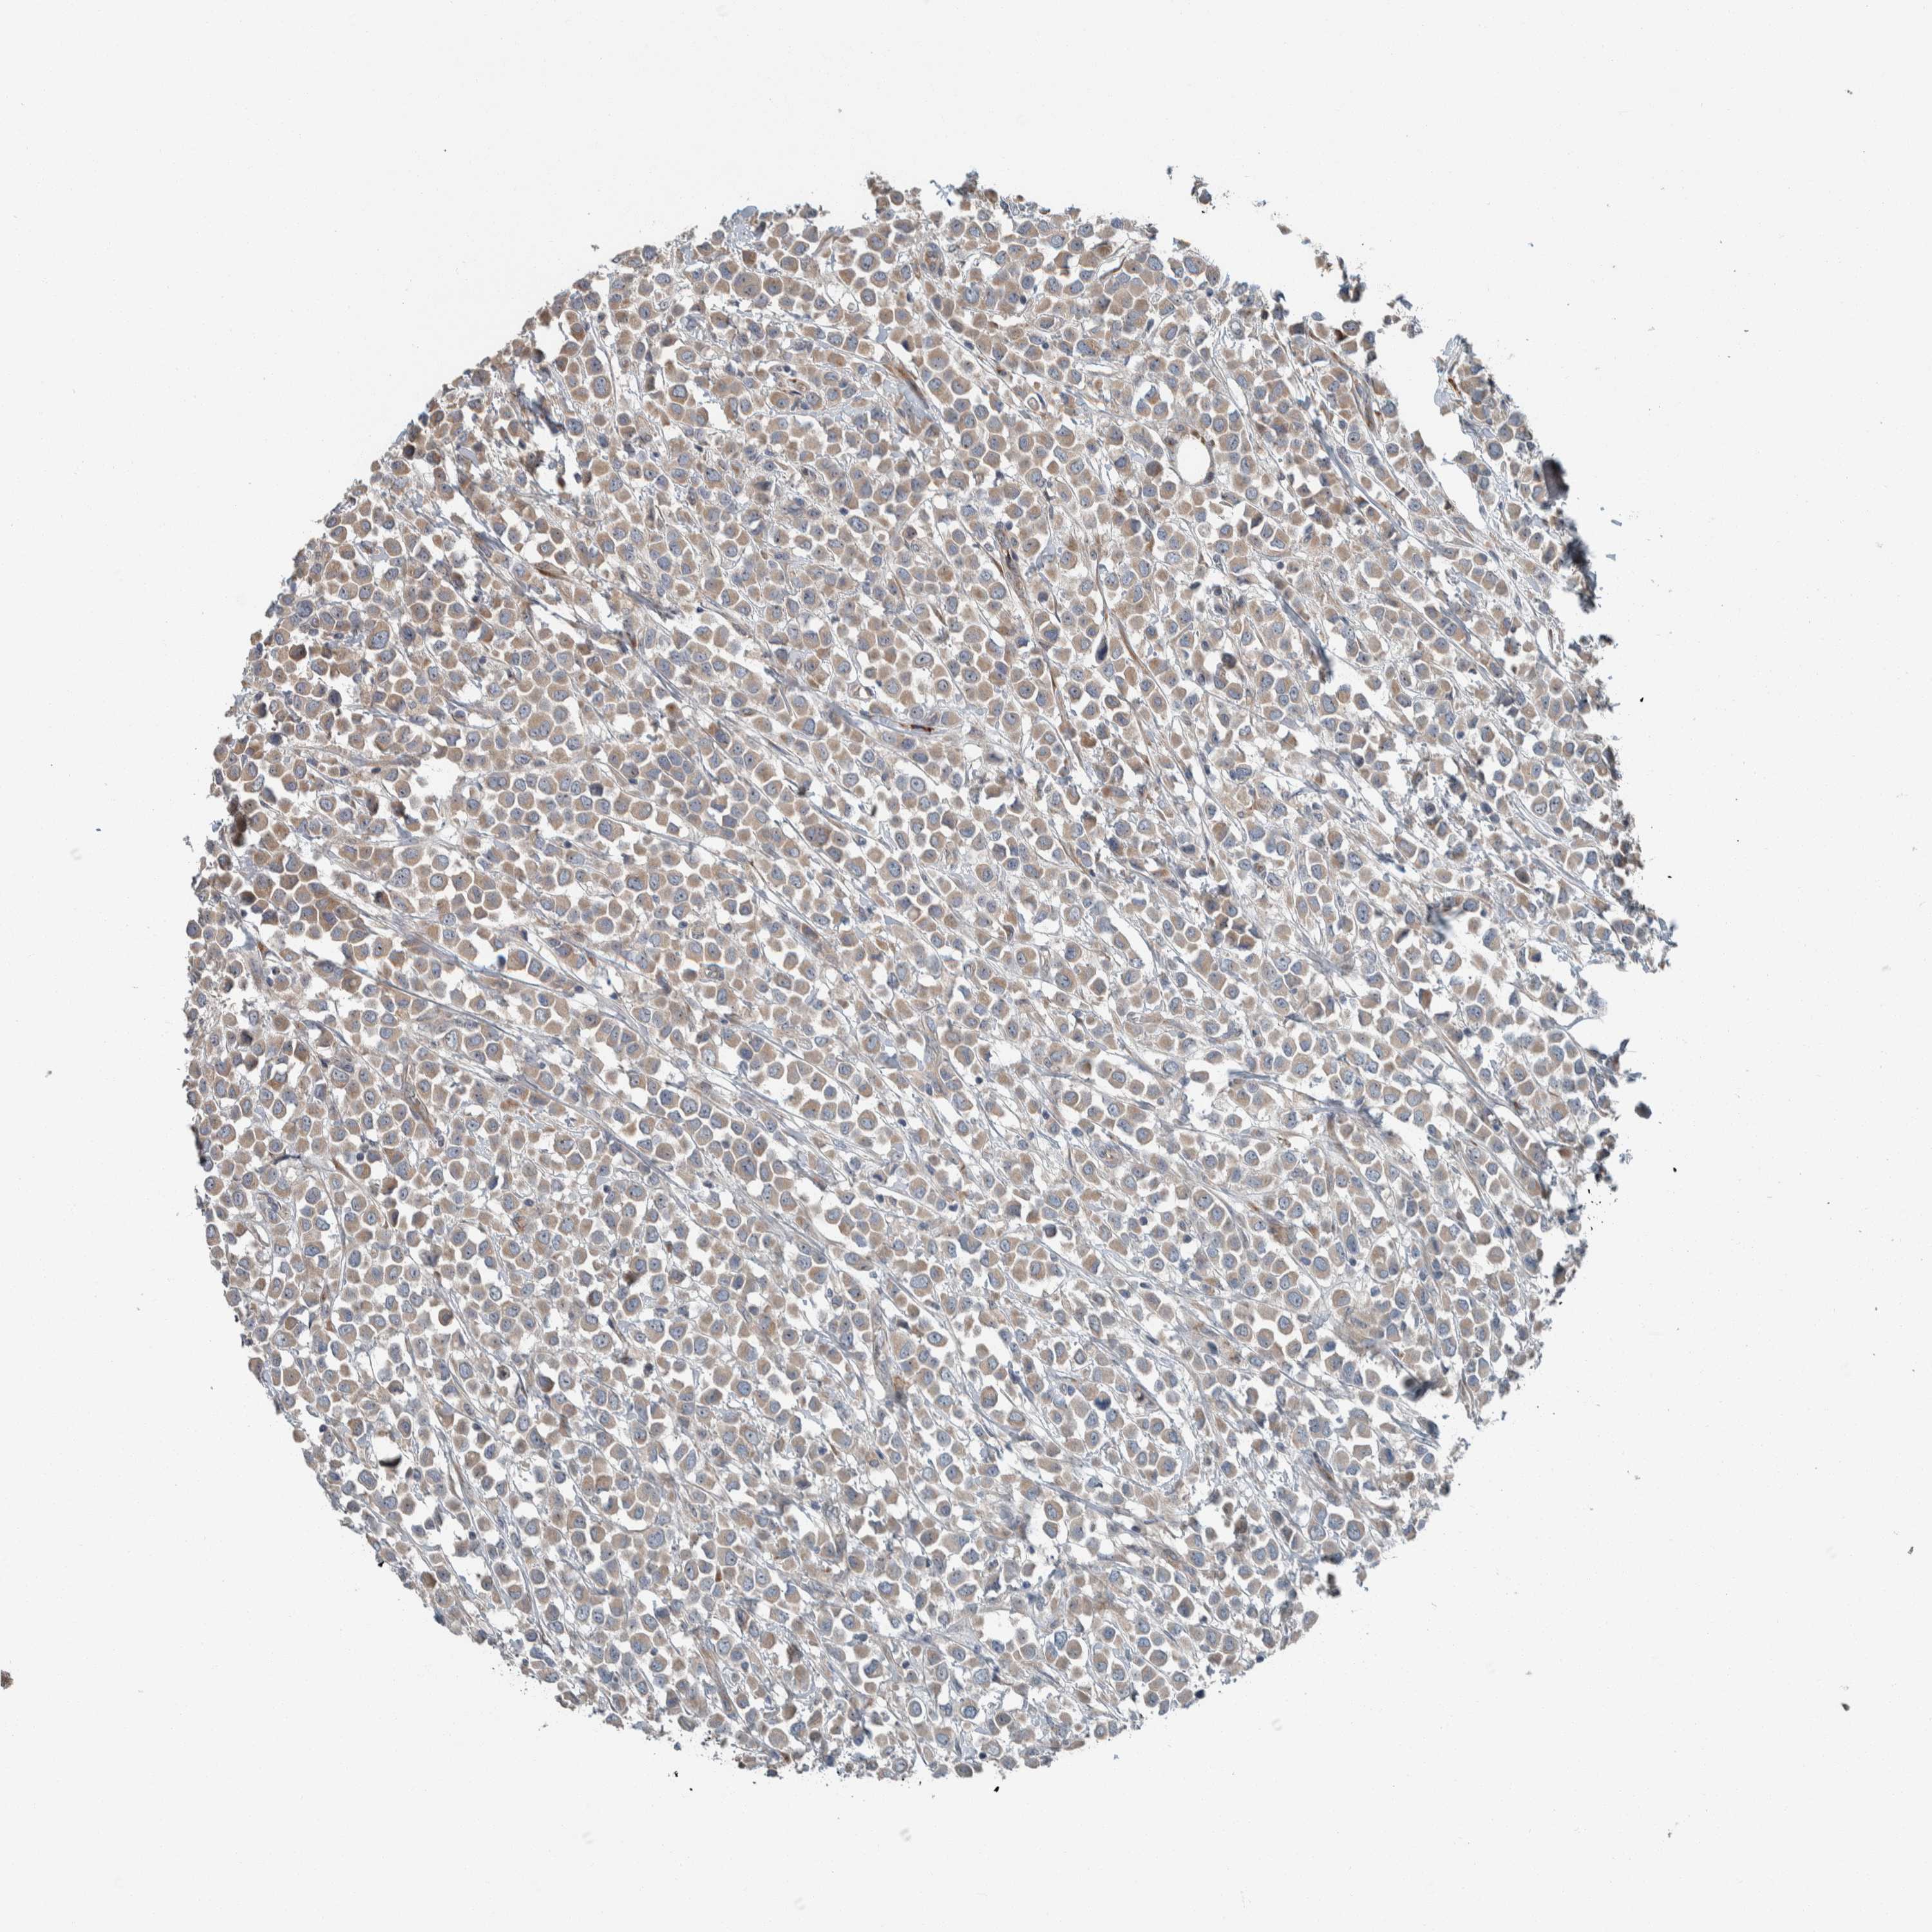

CANCER BREAST CANCER Show tissue menu

BRCA TCGA BRCA VALIDATION PROTEIN EXPRESSION